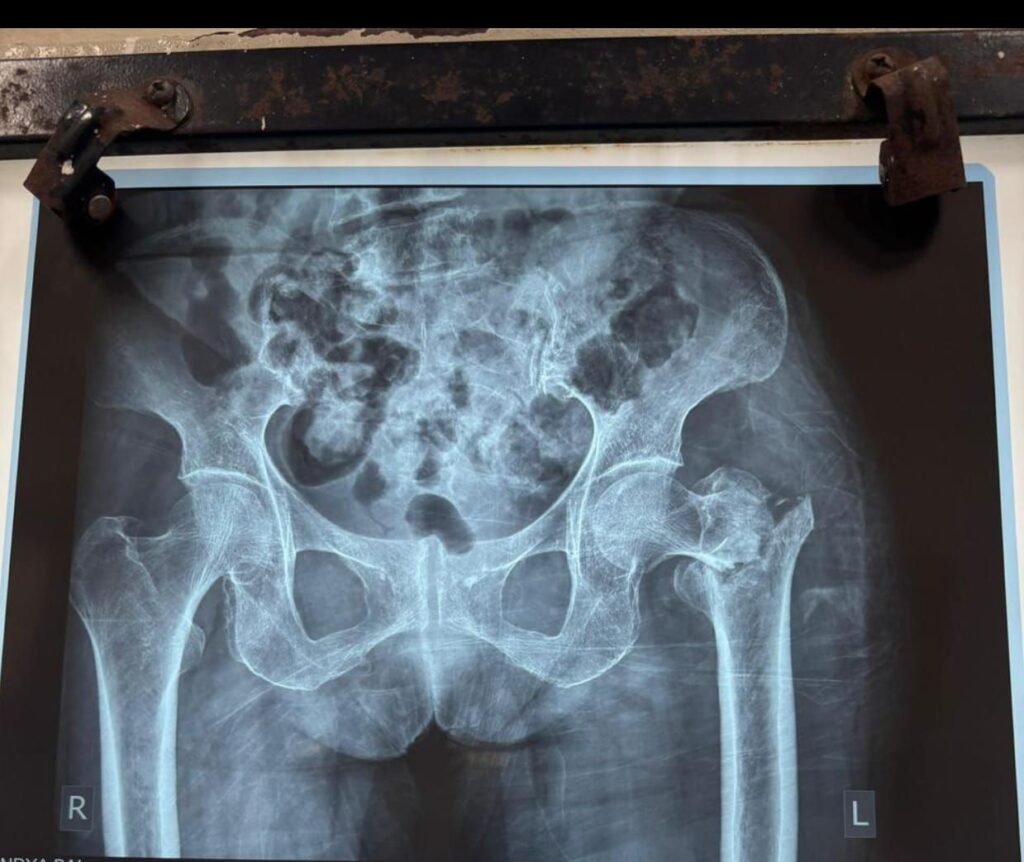

सड़क दुर्घटना में गंभीर रूप से घायल 90 वर्षीय इंडिया बाई के लिए सिम्स (छत्तीसगढ़ आयुर्विज्ञान संस्थान) उम्मीद की किरण बनकर सामने आया है। बाएं कूल्हे की हड्डी बुरी तरह टूट जाने के बाद गंभीर अवस्था में भर्ती कराई गई बुजुर्ग महिला पर अस्थि रोग विशेषज्ञों ने अत्याधुनिक तकनीक से सफल सर्जरी कर नई जिंदगी दी।

अस्थि रोग विशेषज्ञ डॉ. तरुण सिंह ने बताया कि इतनी अधिक उम्र में कूल्हे का फ्रैक्चर जुड़ना बेहद कठिन होता है और मरीज को महीनों तक बिस्तर पर रहना पड़ सकता है, जिससे संक्रमण और अन्य जटिलताओं का खतरा बढ़ जाता है।